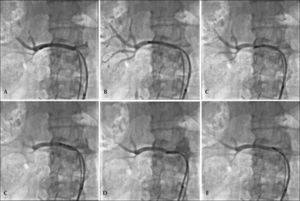

Four to six radiofrequency applications were performed in each renal artery with the irrigated catheter, starting at the most distal portion of the vessel, close to the bifurcation, toward the aorta, respecting the minimum distance of 5mm between each application and the helical arrangement of them. The detailed technique for a percutaneous RSD with an irrigated catheter has been described previously elsewhere by our group.11Figure 1 shows a case in which six radiofrequency applications were conducted in the right renal artery.

Quantitative angiographyFigure 3 exemplifies a quantitative angiography in right renal artery before and 6 months after percutaneous RSD.